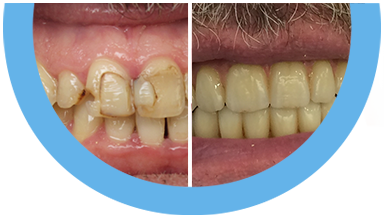

Paciente de 76 anos do sexo masculino

Motivo da consulta: Paciente desdentado total, procurava colocar dentes.

Plano de tratamento: Colocação de 4 implantes superiores e 2 implantes inferiores. Confeção de uma barra superior e colocação de 2 locators® na parte inferior. Confeção de uma prótese superior e outra inferior removível, com encaixes na barra e locators®.

A escolha deste plano de tratamento deve-se ao facto de o paciente querer uma solução total, mas não completamente fixa, uma vez que não tinha muita destreza manual para higienizar uma prótese fixa. Desta forma, conseguiu uma solução bastante retentiva (devido aos encaixes) mas que consegue remover para uma higienização correta.